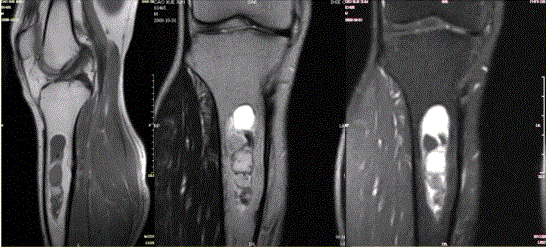

问题 患者女,20岁,右小腿疼痛1周。行双小腿正侧位CR,并行双小腿CT及MR扫描,见下图。 关于病变发生部位,叙述正确的是

选项 A.双侧胫骨干骺端 B.双侧胫骨骨干髓质部 C.双侧胫骨骨干皮质部 D.双侧胫骨骨骺 E.双侧胫骨周围软组织

答案 B